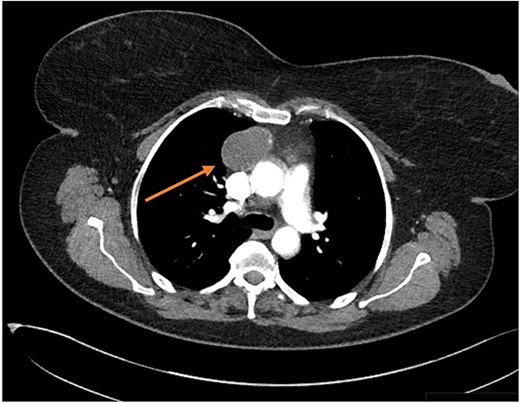

Three months later the patient re-presented with intermittent chest pain associated with a 2-day history of non-productive cough. She was investigated with a chest X-ray and then a contrast CT chest (Figs 1 and 2). Contrast CT chest demonstrated a 20 mm × 40 mm large, slightly lobulated, oval-shaped right anterior mediastinal mass placed more in the superior mediastinum (Fig. 2). The appearance suggested a cystic density within the patchy calcification in the capsule wall. The multidisciplinary team concluded the mass was a thymic or pericardial cyst and planned for surgical excision if there was any progression of the mass.

Bronchogenic cysts are rare congenital defects present due to the abnormal germination of the embryonic foregut that results in a fluid-filled pouch instead of normal bronchial development [5]. Most commonly, they arise due to abnormal budding along the tracheobronchial tree during embryonic development [1]. In adults, bronchogenic cysts are an incidental radiological finding with two-thirds of patients being asymptomatic [1, 2]. It accounts for 50–60% of mediastinal cysts and up to 15% of mediastinal tumours [2]. 79% of BMC are found in the middle mediastinum, 17% in the posterior mediastinum and 3% in the anterior mediastinum. Within the middle mediastinum, paratracheal and tracheal carina are the most common locations [7]. The commonest cystic lesions in the anterior mediastinum are pericardial (9%) and thymic (13%) in origin [4]. Although rare, BMC can be symptomatic due to cyst infection or compression of nearby structures, leading to respiratory distress and cough [8]. These cysts have a small chance of becoming malignant if left untreated [9]. Contrast CT chest is the investigation of choice for suspected BMC, presenting as homogenous, smooth round masses on the middle mediastinum with rare incidence of calcification [5, 8]. Interestingly in this case, the contrast CT thorax demonstrated a large, slightly lobulated, oval-shaped right anterior mediastinal mass with the appearance suggesting a cystic density with patchy calcification in the capsule wall. Histopathological examination can provide a definitive diagnosis and exclude the other differentials. The cyst wall had focal hyaline fibrosis and calcification and contained smooth muscle, bronchial mucous glands and cartilage and lined by ciliated and non-ciliated columnar to cuboidal epithelium, in keeping with BMC. Our patient represents a rare case of BMC due to the presentation and location [8]. Cases of BMC have been reported in literature with majority looking at the mediastinal subtype [10].